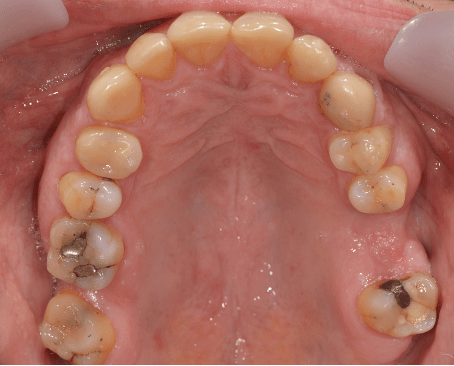

Crowns

Crowns may be used to treat toothwear or broken down teeth. They are often selected where composite has failed, the teeth are too broken down or there is a need to provide a stronger material. This case was managed with surgical crown lengthening and multiple crowns. The lower incisors were treated with composite.